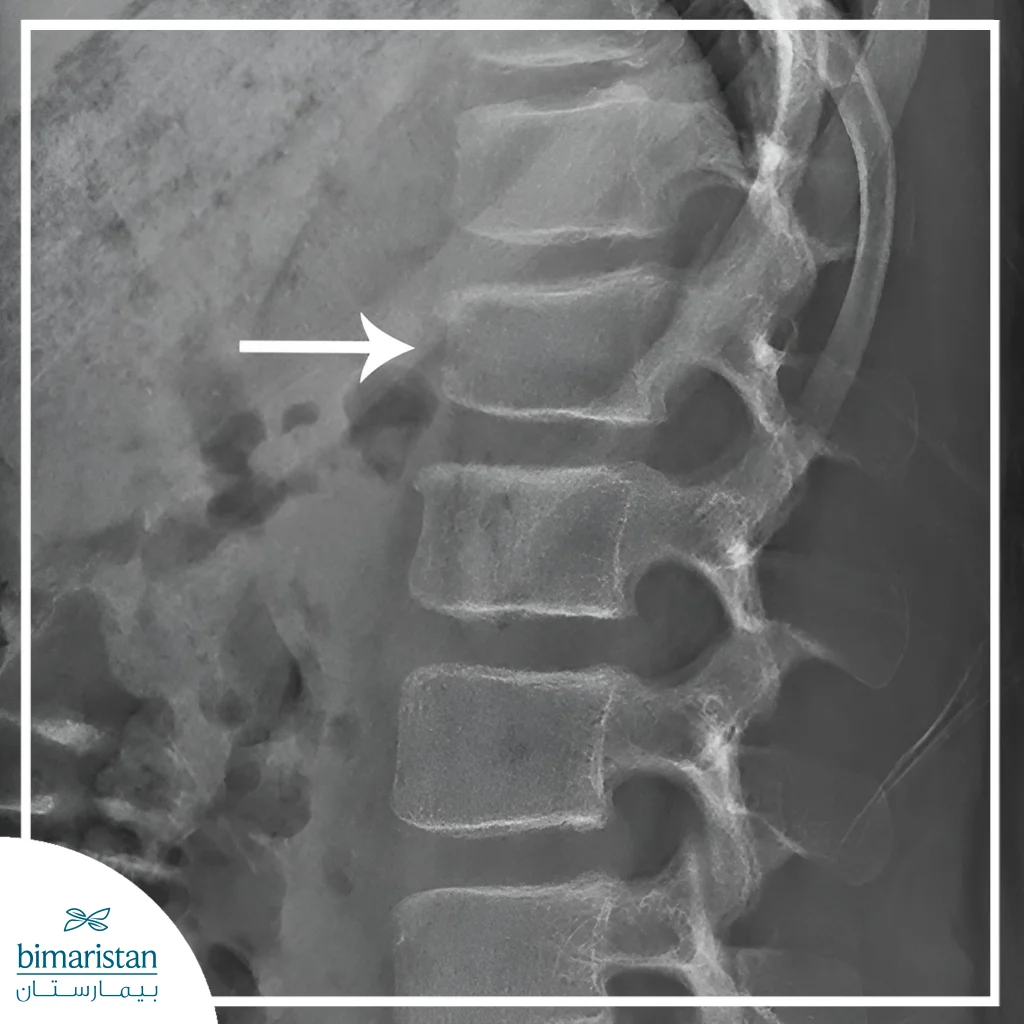

X-rays

X-rays are the first step in imaging to determine the location and type of fracture. Damaged vertebrae are clearly visible and help detect compression or slipped fractures. Multi-angle images can be used to assess the overall stability of the spine before determining the need for any surgical intervention.